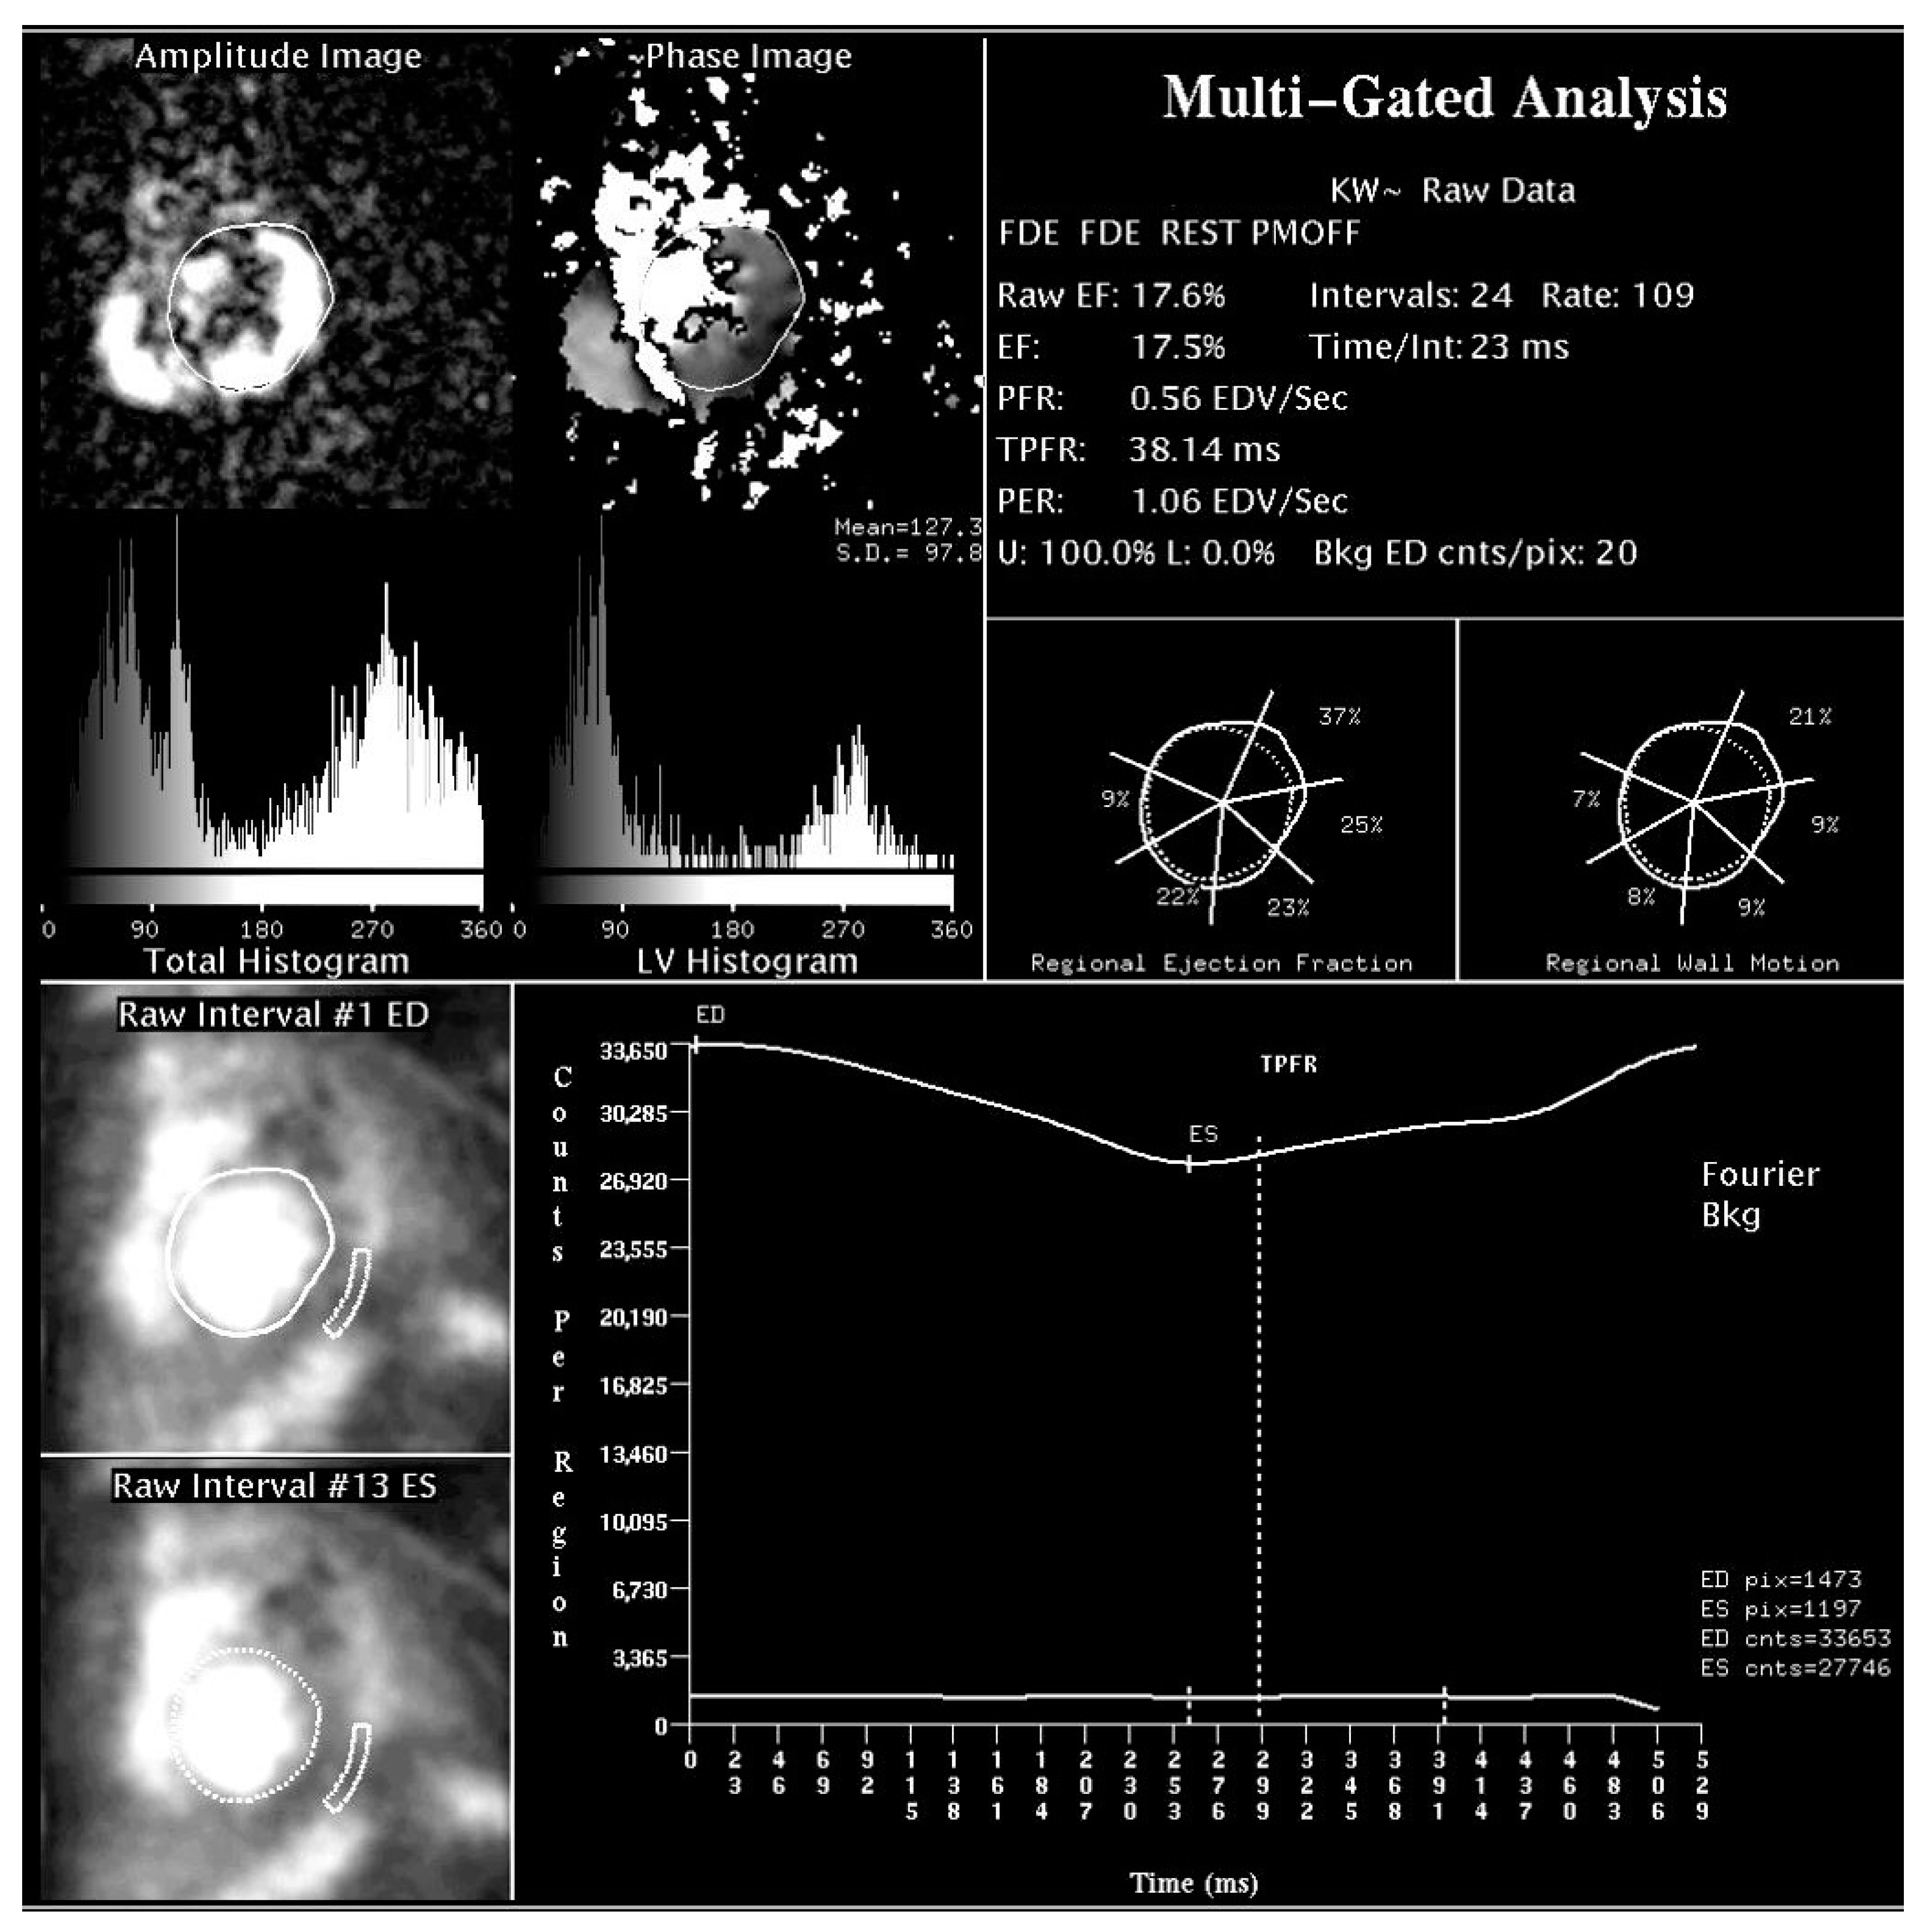

2.1. Assessment of LV Function and Dyssynchrony

- Fauchier, L.; Marie, O.; Casset-Senon, D.; Babuty, D.; Cosnay, P.; Fauchier, J.P. Interventricular and intraventricular dyssynchrony in idiopathic dilated cardiomyopathy: A prognostic study with fourier phase analysis of radionuclide angioscintigraphy. J. Am. Coll. Cardiol. 2002, 40, 2022–2030. [Google Scholar] [CrossRef] [Green Version]

- Valzania, C.; Biffi, M.; Bonfiglioli, R.; Fallani, F.; Martignani, C.; Diemberger, I.; Ziacchi, M.; Frisoni, J.; Tomasi, L.; Fanti, S.; et al. Effects of cardiac resynchronization therapy on right ventricular function during rest and exercise, as assessed by radionuclide angiography, and on NT-proBNP levels. J. Nucl. Cardiol. 2019, 26, 123–132. [Google Scholar] [CrossRef]

- Badhwar, N.; James, J.; Hoffmayer, K.S.; O’Connell, J.W.; Green, D.; De Marco, T.; Botvinick, E.H. Utility of Equilibrium Radionuclide Angiogram-Derived Measures of Dyssynchrony to Predict Outcomes in Heart Failure Patients Undergoing Cardiac Resynchronization Therapy. J. Nucl. Med. 2016, 57, 1880–1886. [Google Scholar] [CrossRef] [Green Version]

- Juarez-Orozco, L.E.; Monroy-Gonzalez, A.; Prakken, N.H.J.; Noordzij, W.; Knuuti, J.; deKemp, R.A.; Slart, R.H.J.A. Phase analysis of gated PET in the evaluation of mechanical ventricular synchrony: A narrative overview. J. Nucl. Cardiol. 2019, 26, 1904–1913. [Google Scholar] [CrossRef] [PubMed] [Green Version]